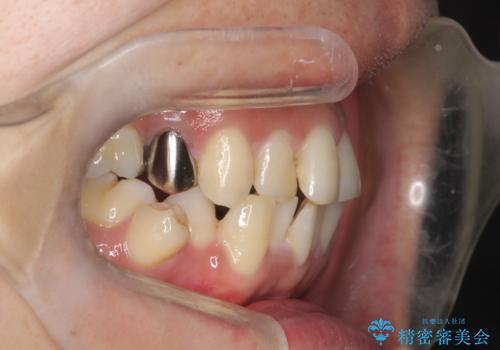

- 治療計画

- 治療計画: 重度の叢生を改善するため、上下左右の小臼歯抜歯を伴う審美ワイヤー矯正を計画しました。抜歯により得られたスペースを利用して歯を整列させ、適切な噛み合わせを目指します。途中、患者様が1年間の海外出張となったため、一時的にワイヤーを外し、保定装置で現状維持を図りました。帰国後に再度審美ワイヤー矯正を再開し、仕上げ調整を行い治療完了を目指します。

重度の叢生により、抜歯を伴う矯正が必要と判断しました。目立ちにくい透明な審美ブラケットを用いたワイヤー矯正を実施しましたが、治療途中での海外出張が決定したため、一度矯正装置を取り外し、保定装置で現状維持を行いました。帰国後に改めて装置を装着し矯正を再開。患者様のライフスタイルに柔軟に対応しながら、最終的には理想的な歯並びと美しい口元を実現しました。